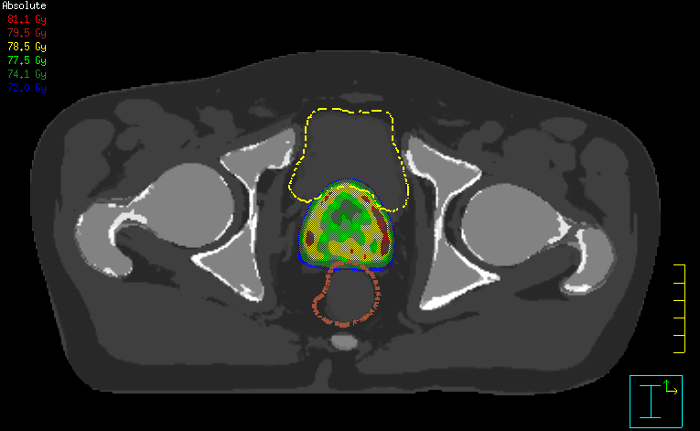

Innovative strategies in MRI-only simulation have made it possible to derive CT-like electron density information from MR imaging data. This capability enables physicians to use MRI as the radiotherapy department’s primary imaging modality for specific applications to eliminate tedious and error-prone CT-MR registration and simplify workflows.

This not only extends the benefits of MRI’s excellent soft-tissue contrast to radiotherapy planning, but it also eliminates arduous, error-prone CT-MRI registration from the process, reducing uncertainties and complexity. MR-only radiotherapy

Our innovative MRCAT (MR for Calculating ATtenuation) clinical applications lets you plan radiation therapy using MRI as primary imaging modality. Within just one, fast MR exam, MRCAT provides both excellent soft-tissue contrast for target and OAR delineation and CT-like density information for dose calculations.

A fully integrated Elekta linear accelerator and 1.5T Philips MRI system usher in the clinical era of high field MR-guided radiotherapy.MR-only simulation in prostate cancer radiotherapy

Clinicians at Finland’s Turku University Hospital have streamlined their workflow for prostate cancer radiotherapy with MR-only simulation.